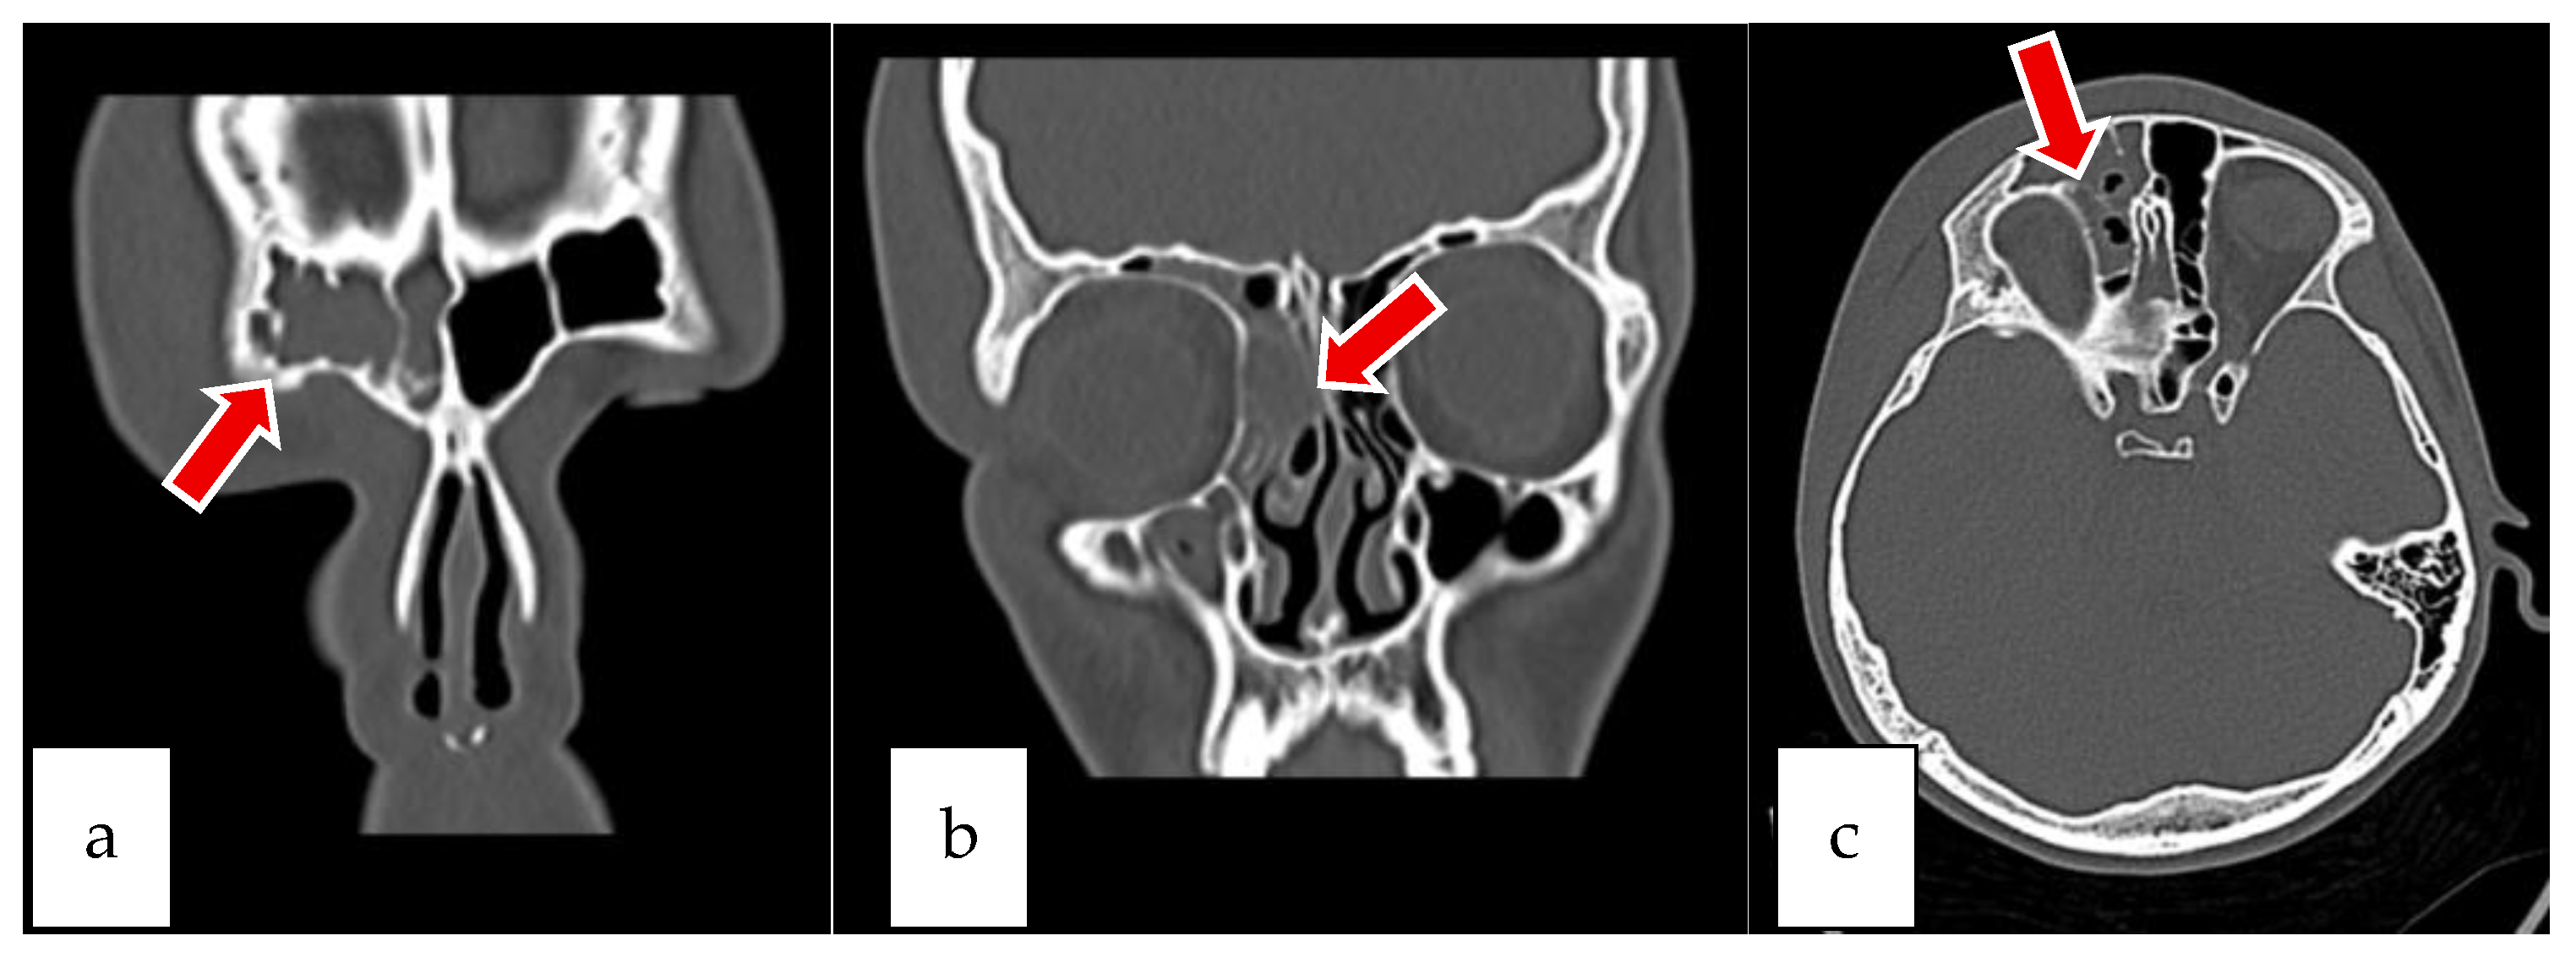

2.1. Case 1